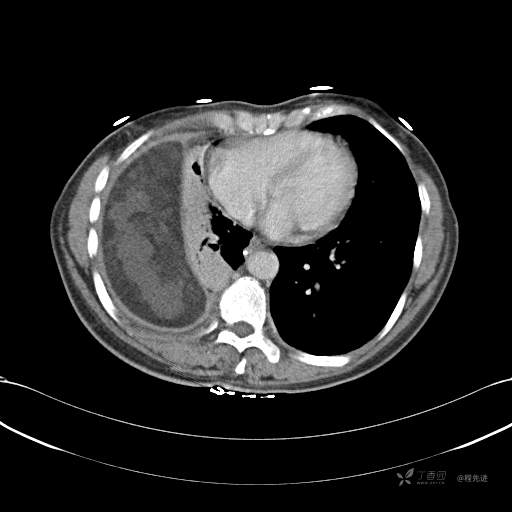

患者性别:女

患者年龄:51岁

简要病史:胸闷半年